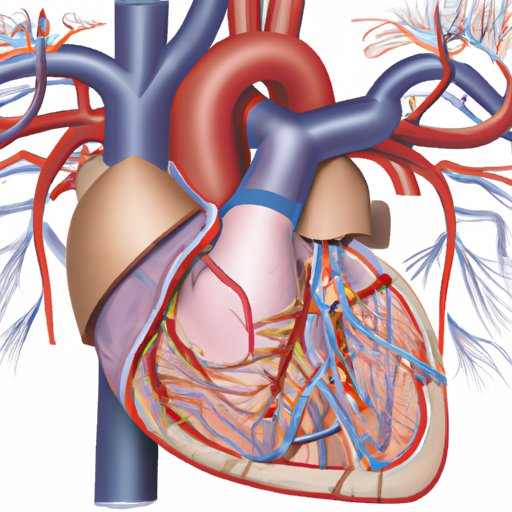

The Pulmonary Trunk: Understanding the Heart’s Connection to the Lungs

The pulmonary trunk plays a vital role in regulating the amount of oxygenated blood in the body. This article will explore everything you need to know about the heart’s connection to the lungs, with a focus on the anatomy of the heart, the function of the pulmonary trunk and its connection to the right ventricle, and common issues associated with the pulmonary trunk.

Why Arteries Should Be Considered an Organ: A New Understanding of Vascular Function

This article explores why arteries should be redefined as organs based on their vital functions in the circulatory system. It includes an overview of the definition of an organ, historical and current classification of arteries, their functions, and insights from experts, along with the implications of including arteries as organs in medical research and treatment.

The Atrium: Anatomy, Function, and Significance in Medicine, Architecture, and History

Explore the anatomy, function, and historical significance of atria in medicine, architecture, and history. Learn about the crucial role of atria in the circulatory system and their use as a key design feature in building construction.